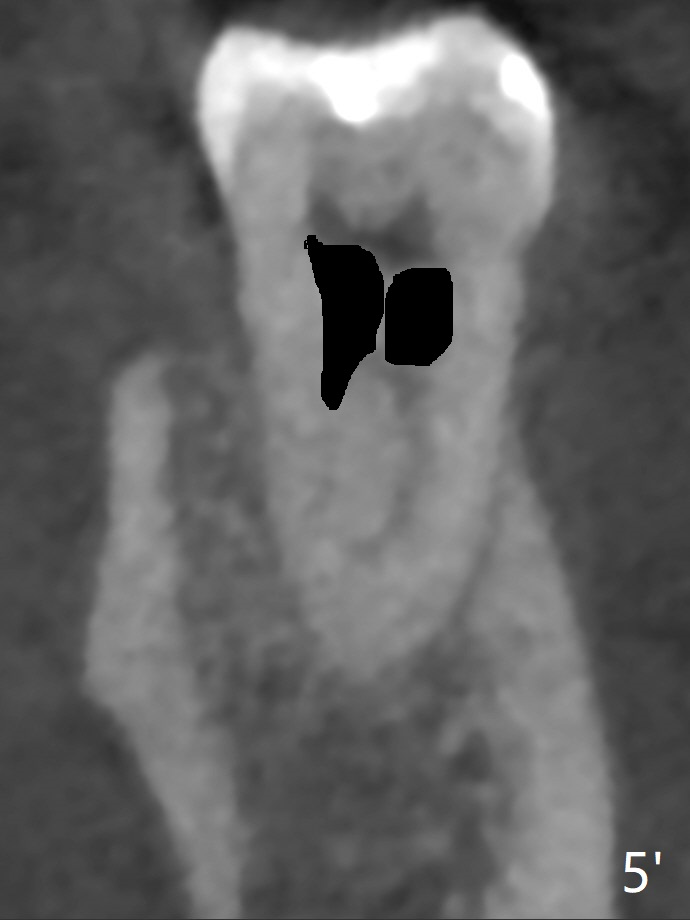

A 61-year-old man may have referral pain between #17 and 18. The canals at #18 are narrower than those at #17 (Fig.1-3). If #18 needs RCT, blocks should be removed (Fig.4-6 vs. 4'-6').